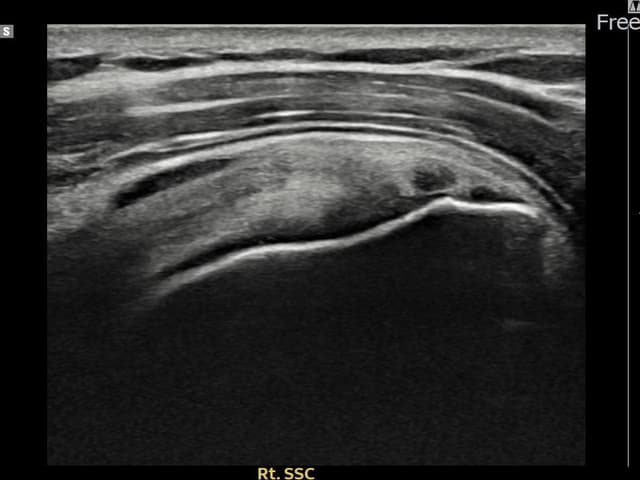

[촬영시기:22.09.05~22.12.08]

[어깨인대 축소봉합술] 우측 어깨 통증과 야간 통증으로 수면 장애가 있어 내원하셨습니다.